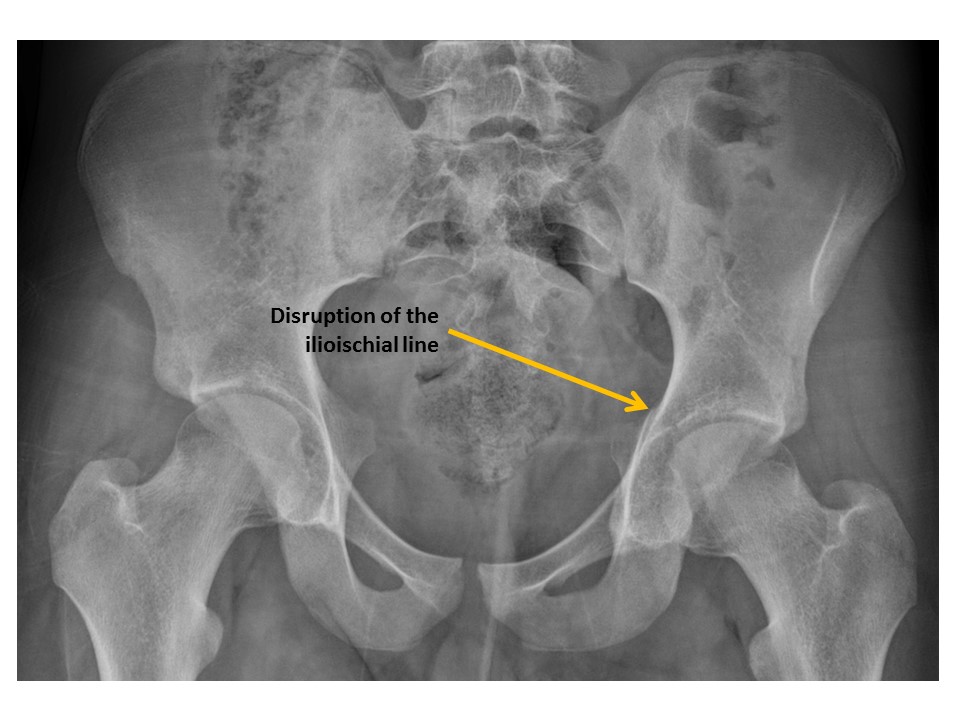

Ilioischial lines are disrupted. [Yes/No]

Iliopubic (iliopectineal) lines are disrupted. [Yes/No]